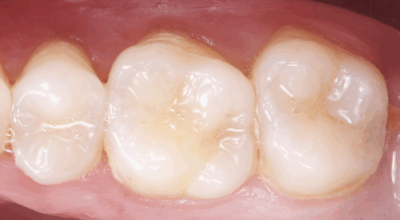

Clinical case of tooth 17 (upper right second molar)

Indirect pulp capping: 96.4% success rate